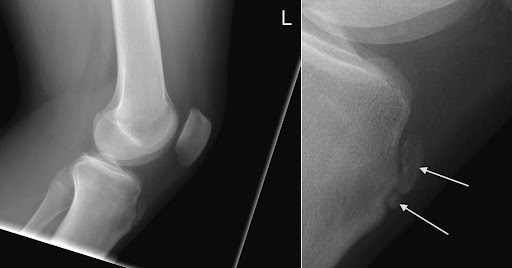

• X-ray (Lateral view): 진단에 필수적이진 않음, 경골 결절의 종창, 골편 형성(ossicle formation), 분절화 소견 가능